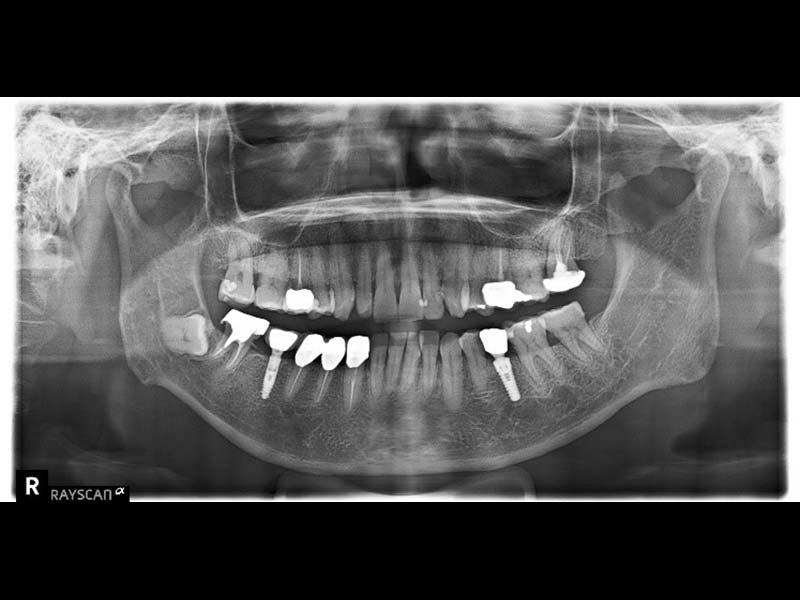

殘餘牙齒拔除後,待傷口癒合,使用口掃機取得全口3D模型,製作數位導板和治療計畫,精準定位將組織及骨膜切開,將植體鎖入凹槽並在齒槽骨裡面,讓植體周圍牙肉保持在最佳狀態。中間等待約3-6個月的時間,讓植體與骨肉整合,待復原完成後就可以取模製作植牙假牙了。

拍攝電腦斷層影像和口腔口掃並製作治療計畫